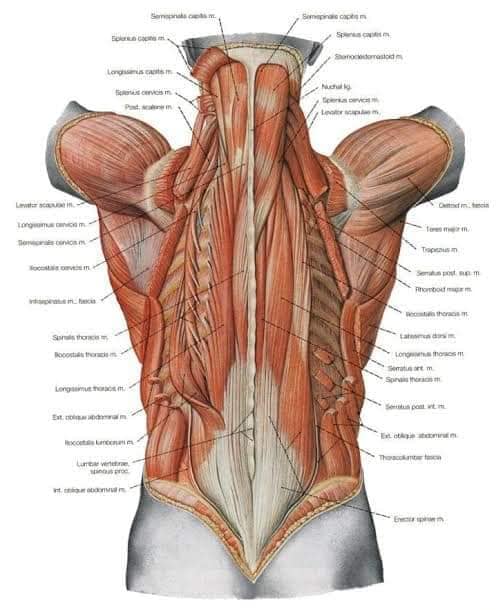

Спинні м'язи

Спинні м'язи виконують функції підтримки хребта, а також дозволяють здійснювати рухи тулуба.

Поверхневі спинні м'язи

М'язи, що піднімають лопатку: Трапецієподібний м'яз: великий м'яз, що покриває верхню частину спини. Його функція - підтримка і рух лопаток, а також забезпечення стабільності хребта.

М'язи, що ведуть лопатку до хребта: Широкий м'яз спини: великий м'яз, що розташований в нижній частині спини. Він відповідає за рухи плечей і лопаток, а також за розширення верхньої частини тулуба.

Глибинні спинні м'язи

М'язи, що забезпечують стабільність хребта: М'язи, що розташовані між хребцями: включають мускулатуру, яка забезпечує стабільність і підтримку хребта, а також дозволяє здійснювати рухи хребта.

М'язи, що здійснюють ротацію та нахили

М'язи, що забезпечують ротацію хребта: Ротаційні м'язи: допомагають у здійсненні обертальних рухів тулуба, а також у підтримці рівноваги і стабільності хребта.